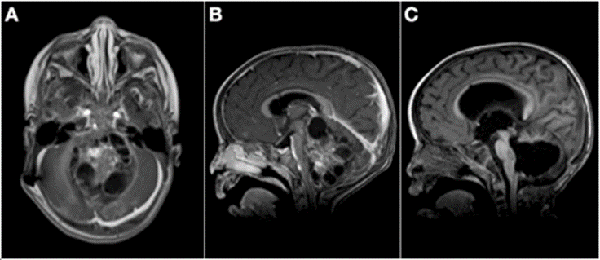

Figura 3: A) Paciente de 11 meses de vida, sexo masculino, que presentó macrocefalia, irritabilidad y vómitos, IRM de cerebro que mostró extensa lesión cerebelosa de aspecto nodular con intenso realce con el contraste endovenoso. B) IRM corte sagital de dicha lesión. C) IRM de cerebro postquirúrgica luego de dos cirugías de exploración y exéresis, diagnóstico de meduloblastoma desmoplásico nodular. Realizó quimioterapia y actualmente presenta un leve retraso neuromadurativo.

Figura 4: A) Paciente de 21 meses de vida, sexo masculino, que consultó por SHE y deterioro del sensorio. IRM de cerebro corte axial que evidenció lesión heterogénea en IV ventrículo y vermis con compromiso de tronco del encéfalo. B) IRM de cerebro corte sagital: ocupación de la totalidad del IV ventrículo. C) IRM de cerebro post quirúrgica, se evidenció exéresis tumoral completa, diagnóstico de ATRT de fosa posterior. Paciente falleció por progresion de enfermedad a los 6 meses.